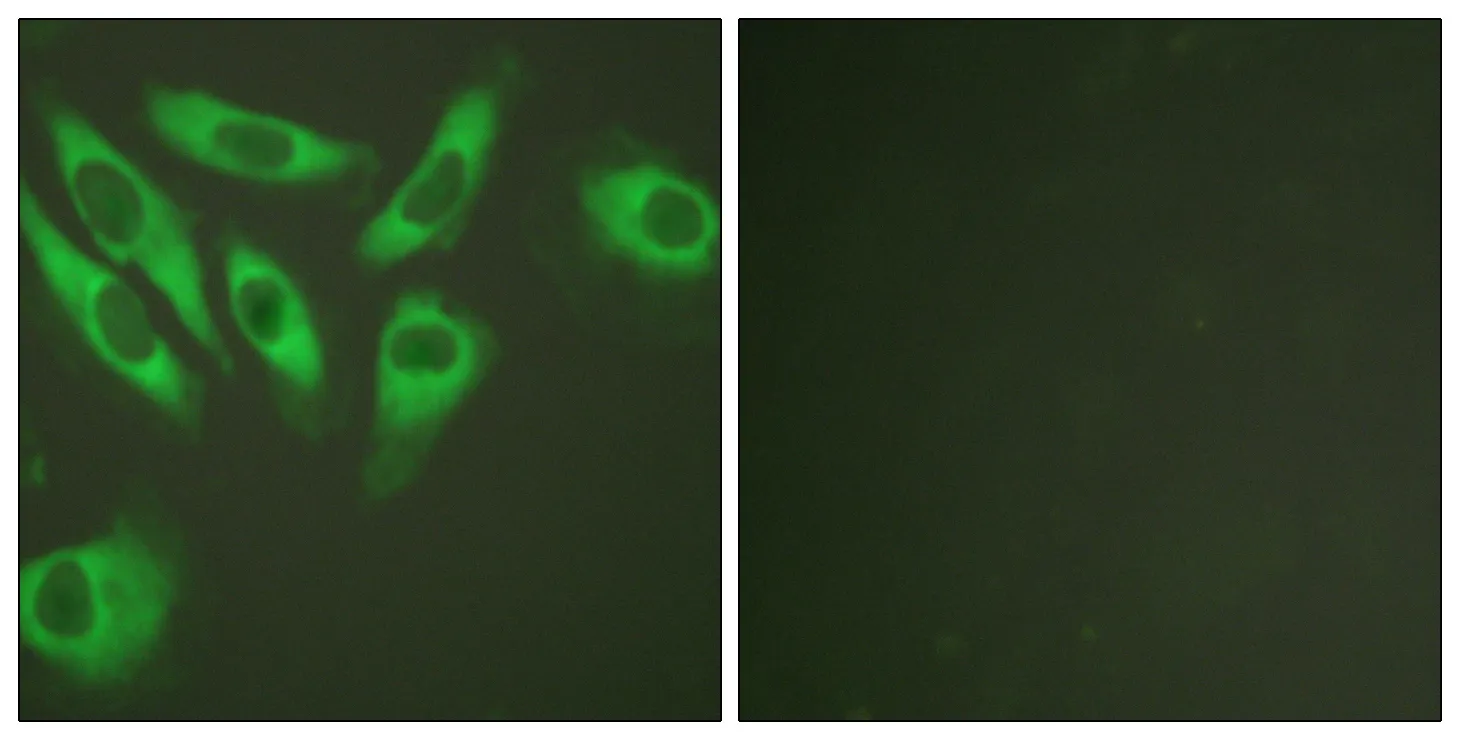

Glut4 Rabbit Polyclonal Antibody

Cat: APRab11504

Size1:50μl Price1:$118

Size2:100μl Price2:$220

Size3:500μl Price3:$980

Size2:100μl Price2:$220

Size3:500μl Price3:$980